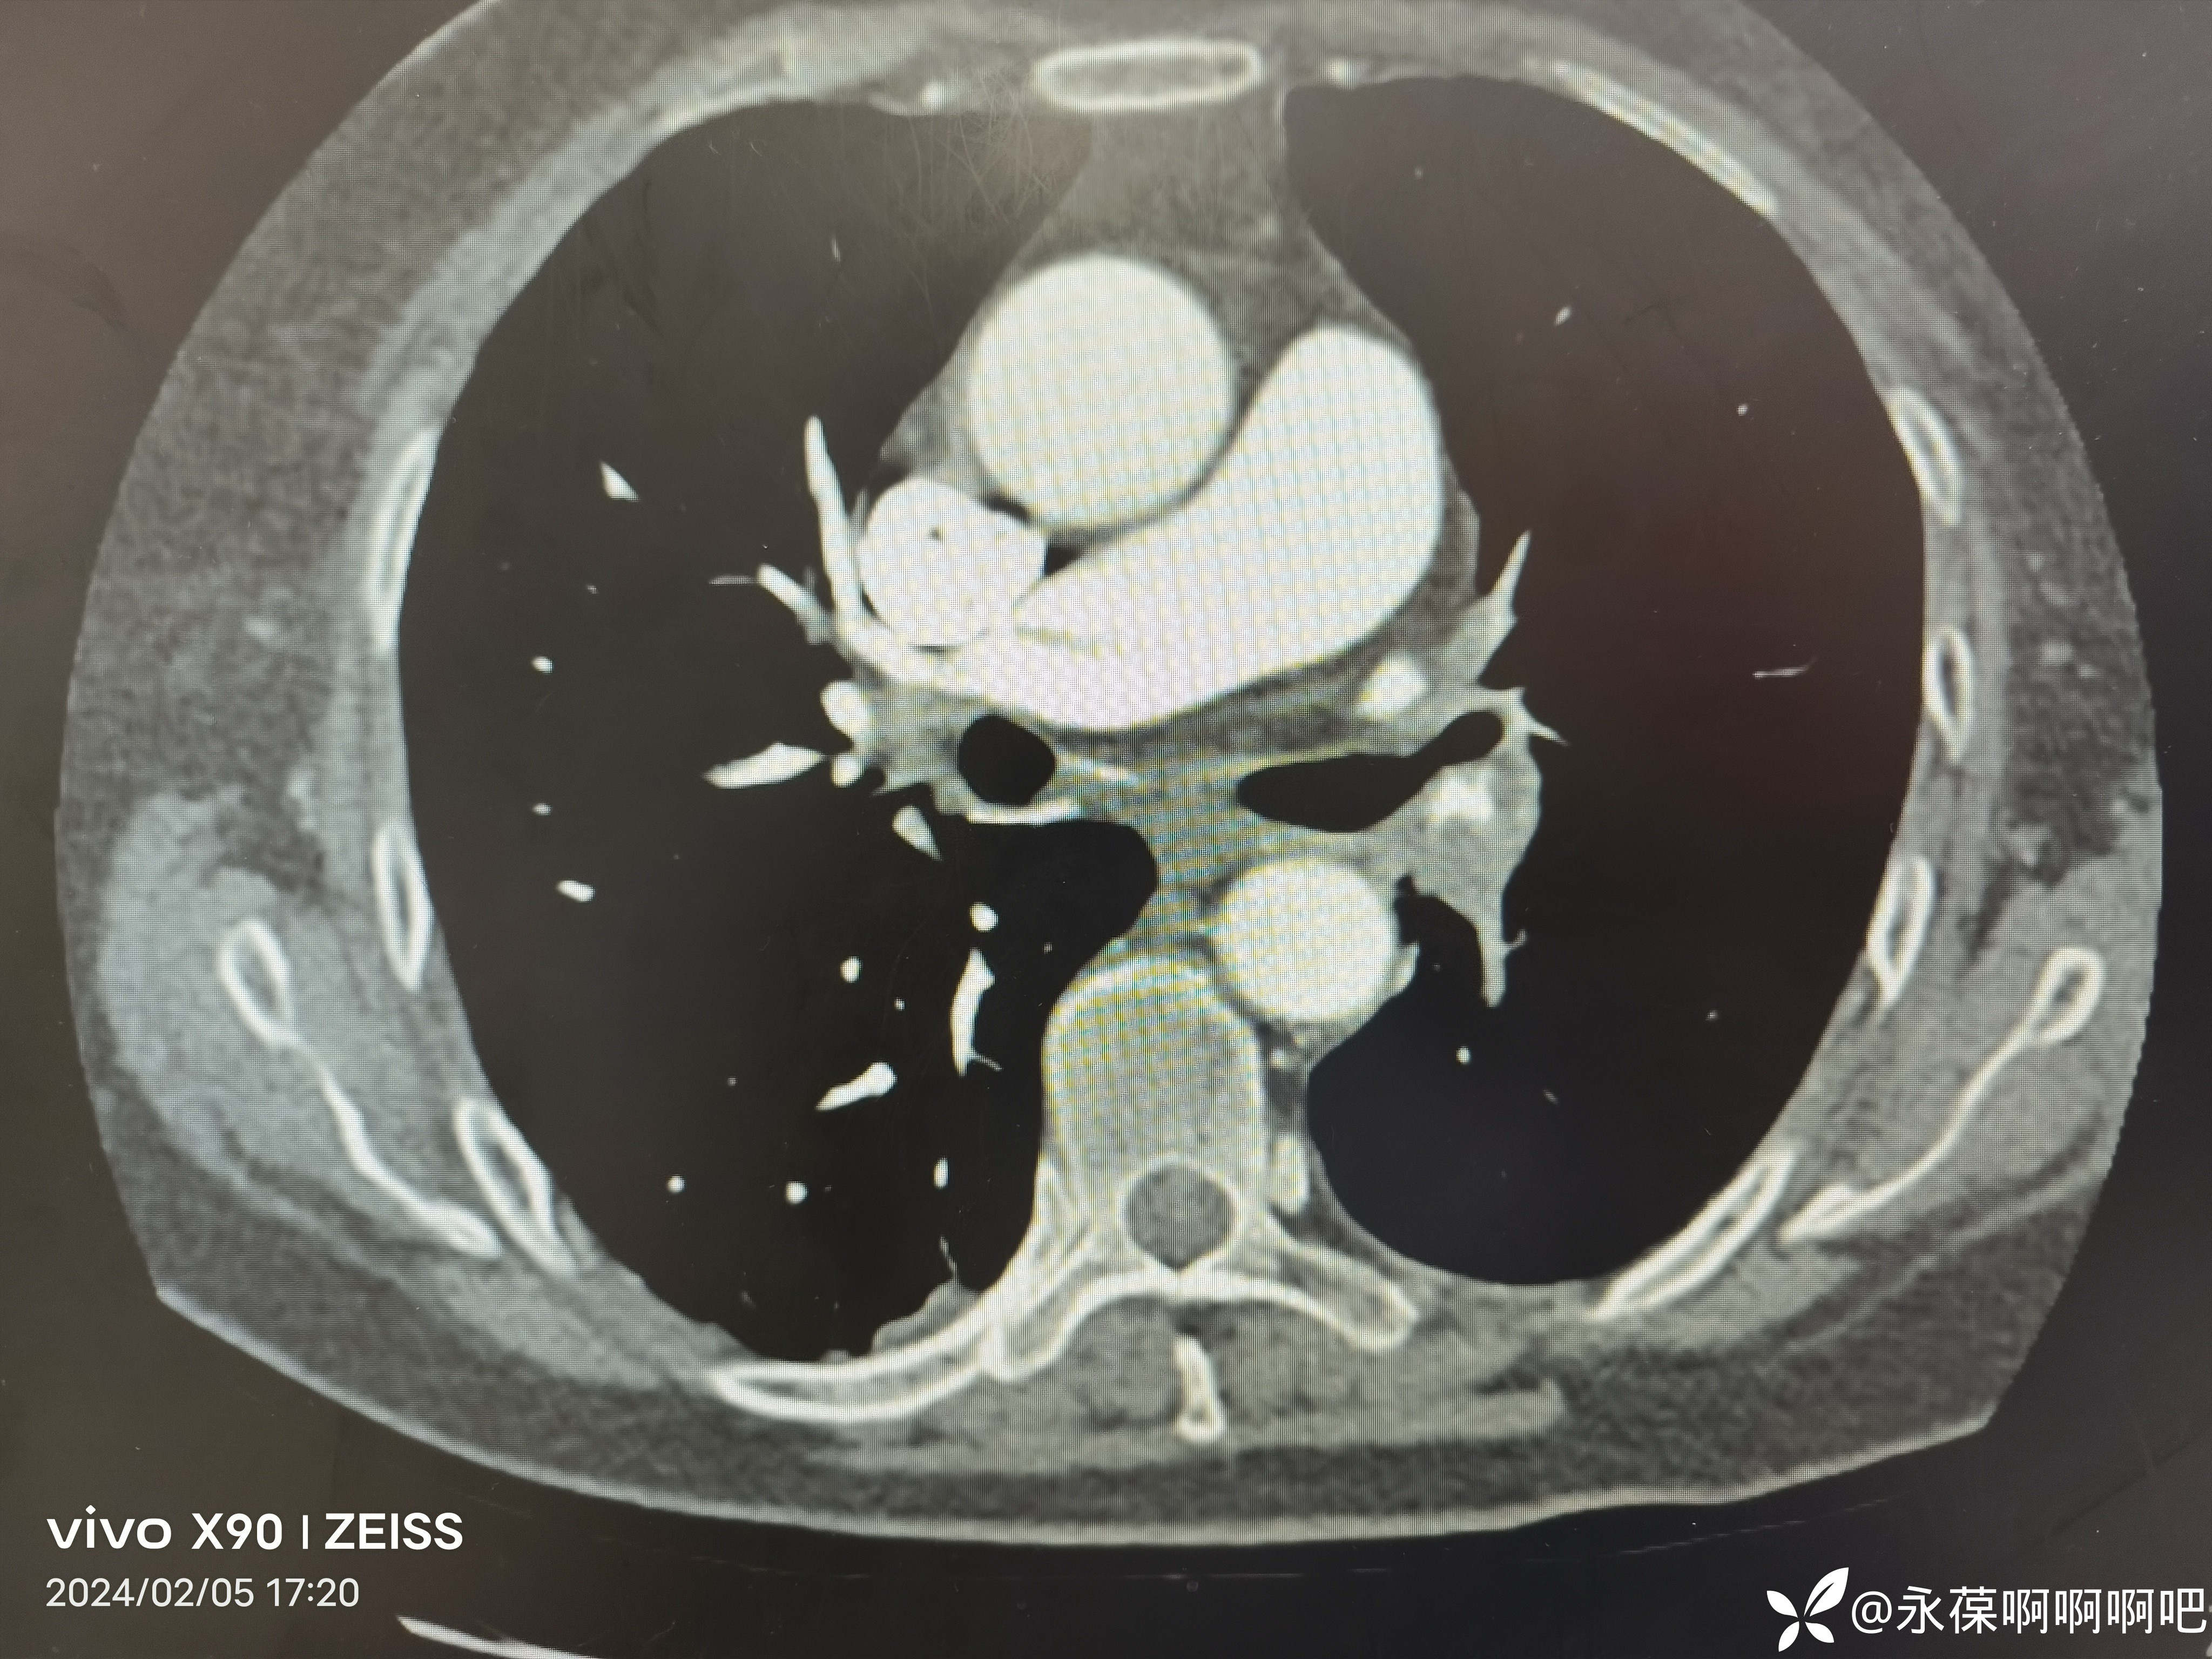

肺动脉CTA:左右肺动脉干及其分支多发栓塞。